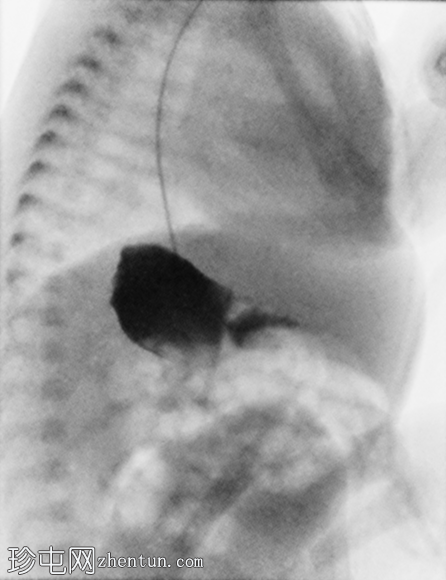

肺容量在正常范围内。可见轻度弥漫性颗粒状阴影。心脏大小和形态正常,心尖指向左侧。

腹部肠道气体分布无梗阻。经食管插管延伸至右侧腹部,提示胃位于右侧。左上腹密度增高,提示肝脏轮廓。